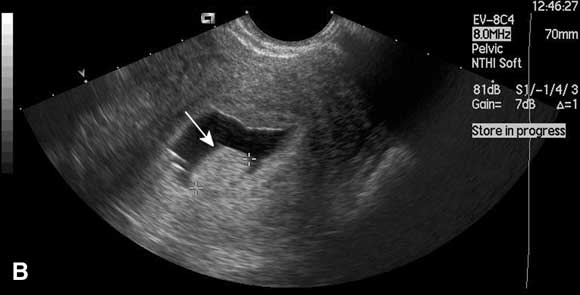

In this case, saline infusion sonohysterography confirmed the presence of a submucous fibroid. This was resected hysteroscopically under general anaesthesia, leading to a substantial reduction in menstrual bleeding and a reduction in dysmenorrhoea.

In this technique, saline is instilled transcervically into the uterine cavity to distend the uterus and increase contrast, and the cavity is visualised using ultrasound (Box). Saline infusion sonohysterography is more accurate than transvaginal ultrasound alone in diagnosing submucous fibroids and endometrial polyps in women with abnormal uterine bleeding,12 and can be performed in the outpatient clinic. An alternative form of imaging is diagnostic hysteroscopy, but this is invasive and often performed under general anaesthesia. Use of saline infusion sonohysterography has been shown to reduce the need for diagnostic hysteroscopy.13